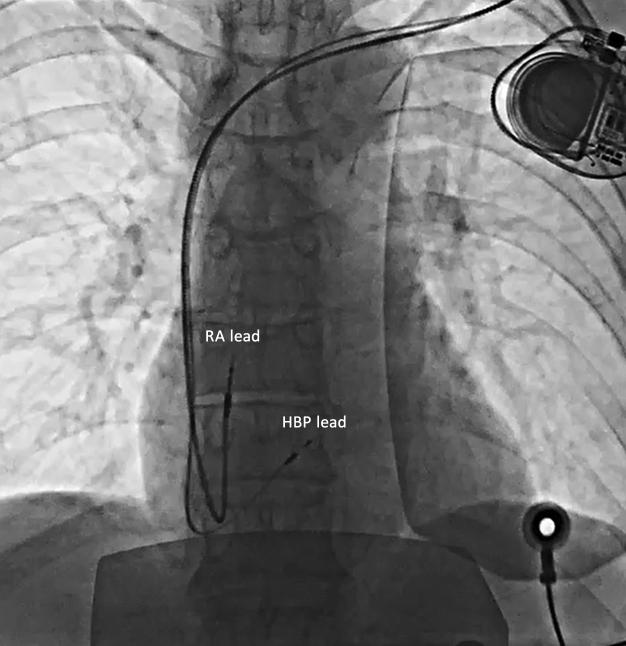

A 49-year-old woman presented with exercise-induced chest discomfort during long-distance running that was occasionally present during rest. Significant coronary artery disease was excluded and a diagnosis of "painful left bundle branch block (LBBB) syndrome" was made after correlation of LBBB aberrancy with symptoms during Holter monitoring. The patient underwent confirmatory testing consisting of rapid atrial pacing below and above 130 beats per minute, the rate cut-off for LBBB manifestation. His bundle pacing implantation was performed resulting in both non-selective and selective morphologies depending on output, both of which manifested with a painless narrow QRS regardless of rate. She was rendered completely pain free during long-distance running and remains so 6-months later. Her pain at rest, now thought to be due to severe anxiety secondary to her painful LBBB, has also subsided. Exercise-induced, painful LBBB is a rare phenomenon that manifests as chest discomfort when LBBB is present. This disease is frequently misdiagnosed as coronary angina, has limited medical treatment options, and can be disabling. HBP is an attractive treatment for this syndrome in an effort to avoid electromechanical dyssynchrony, the presumed mechanism of discomfort. This case report adds to the growing literature of painful LBBB syndrome and its effective treatment with HBP, with the added caveat that it can present with persistent symptoms at rest, in the setting of enhanced anxiety. HBP should be considered early on in the treatment of such patients.

一名49岁女性在长跑时出现运动诱发的胸部不适,休息时偶尔也会出现。排除了严重冠状动脉疾病,在动态心电图监测中将左束支传导阻滞(LBBB)异常与症状相关联后,诊断为“疼痛性左束支传导阻滞综合征”。患者接受了验证性测试,包括在每分钟130次心跳上下进行快速心房起搏,这是LBBB表现的心率临界值。进行了束支起搏植入,根据输出不同产生了非选择性和选择性形态,无论心率如何,两者均表现为无痛性窄QRS波。她在长跑时完全没有疼痛,6个月后仍然如此。她休息时的疼痛现在认为是由于疼痛性LBBB继发的严重焦虑所致,也已减轻。运动诱发的疼痛性LBBB是一种罕见现象,表现为存在LBBB时的胸部不适。这种疾病常被误诊为冠状动脉性心绞痛,治疗选择有限且可能致残。心脏再同步化治疗(HBP)是治疗该综合征的一种有吸引力的方法,旨在避免电机械不同步,这被认为是不适的机制。本病例报告增加了关于疼痛性LBBB综合征及其HBP有效治疗的文献,此外还需注意,在焦虑增强的情况下,该综合征可能在休息时出现持续症状。对于此类患者的治疗应尽早考虑HBP。